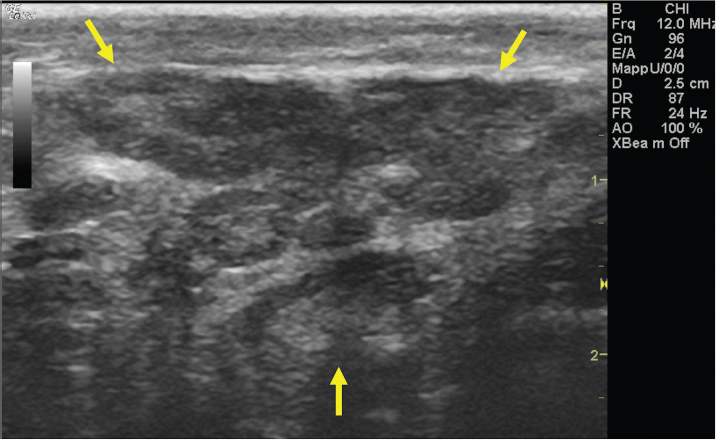

Fig. 2. A 20-G intravenous catheter placed into the right congestive facial vein in the anesthetized horse. The left jugular vein appeared as an anechoic tubular structure which collapsed under the probe pressure, the color Doppler examination revealed normal blood flow within the vessel (Fig. 3). Bi-dimensional ultrasonography of the right jugular vein showed a heterogeneous, non-cavitating, hypoechoic structure occluding a narrowed right jugular vein for about 30 cm of length localized in the proximal and mid-portion of the neck compatible with a thrombus (Fig. 4). The color Doppler examination showed blood flow through the lateral portions of the thrombus in the cranial and mid-portions of the right jugular vein (Fig. 5). Cranially to the thrombus, a marked distension of the maxillary and linguofacial veins was evident, with a turbulent and echogenic flow; the latter was compatible with blood stasis near the thrombus (Fig. 6). Caudally to the thrombus, the right jugular vein presented reduced diameter, thickened walls, and normal blood flow (Fig. 7). The cranial part of the thrombus originated from a heterogeneous scare tissue, localized at the level of the right mandibular angle (Fig. 8). After injection of the first saline contrast bolus in a right facial vein, no microbubbles appeared in the right jugular vein, caudally to the thrombus, proving the presence of a complete right jugular vein occlusion. On the contrary, after injection of the second bolus, microbubbles were visualized in the left jugular vein as small, intense, echo signals within the vein lumen, demonstrating the presence of collateral circulation that drained the blood from the right facial veins to the left jugular vein (Fig. 9). Venography results confirmed the complete occlusion of the right jugular vein and the presence of submandibular venous collaterals that connected the right facial veins with the left jugular vein (Figs. 10 and 11). Based on the previous results, the diagnosis of JVT with complete occlusion of the vessel lumen was confirmed. The horse’s owner refused any proposed medical or surgical therapy.

Fig. 7. Bi-dimensional ultrasonographic image of the right jugular vein, caudally to the thrombus, in longitudinal section (arrows). No microbubbles appeared caudally to the thrombus, following injection of the first saline contrast bolus. DiscussionThe description of the present clinical case shows that SCU is a valid tool to assess vessel patency and presence of collateral circulation in JVT. Two-dimensional ultrasonography is useful in diagnosing JVTP and JVT and in monitoring the progression of the disease (Gardner et al., 1991; Borghesan et al., 2018). Vessel patency is usually assessed by venography and Doppler ultrasonography (Hussni et al., 2009; Borghesan et al., 2018). However, venography requires repeated x-ray exposure and Doppler ultrasonography is highly operator and equipment-dependent. Furthermore, the Doppler color examination allows evaluating blood flow presence and direction only in small portions of the vessel at a time; therefore, when the thrombus is 15–44 cm long, as happens in the JVT of horses (Borghesan et al., 2018), it does not give a global view of the obstructed vessel. On the contrary, the SCU test allows a real distinction between total and partial vessel occlusion, it can be easily performed and objectively interpreted using standard ultrasound equipment, it is not expensive and, finally, it does not require x-ray exposure.

Fig. 9. Bi-dimensional ultrasonographic image of the left jugular vein in longitudinal section (arrows). Microbubbles appeared as small, intense, echo signals that passed in the vein lumen following agitated saline injection.